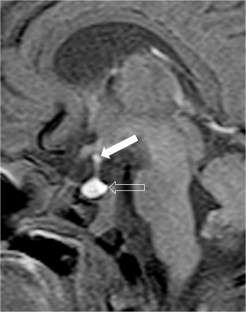

We selected pediatric head MRI examinations from 2005 to 2017 based on the finding of a double midline sellar and suprasellar bright spot on T1-weighted sequence. Medical history, physical examination, pituitary hormonal profile and bone age evaluation were extracted from the medical record of the selected patients. An experienced pediatric neuroradiologist reviewed head MRIs, which were performed on 3-tesla (T) magnet and included at least sagittal T1-weighted imaging centered on the sella turcica obtained with and without fat suppression.

In six cases, two midline bright spots were identified on T1-weighted sequences obtained both with and without fat suppression. While one spot was located at the expected site of the neurohypophysis in the posterior sella, the second one was in the region of the median eminence, suggesting partial ectopic posterior pituitary gland. Growth hormone deficiency, either isolated (n=1) or combined with thyroid stimulating hormone deficiency (n=1) was found. None of the children had clinical signs of posterior pituitary dysfunction.

Fig. 3